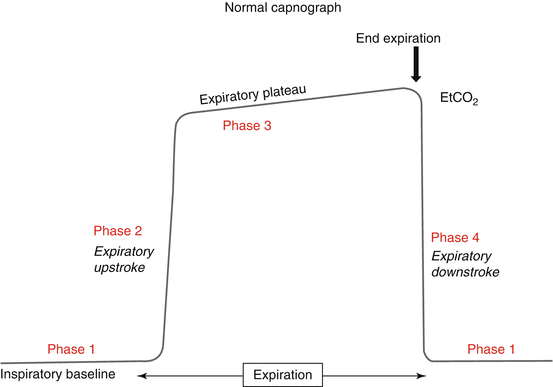

Waveform Capnography:

What is Waveform Capnography?

Waveform capnography measures the amount of carbon dioxide (CO2) in exhaled air, which provides information about the patient’s ventilatory status. It displays this information in both numerical form (end-tidal CO2, or EtCO2) and as a waveform, allowing for continuous monitoring.

Components of the Capnography Waveform

The capnography waveform, also known as a capnogram, consists of several phases:

1. Phase I : Baseline, representing exhalation of CO2-free gas from the anatomical dead space.

2. Phase II: Expiratory upstroke, where CO2 from alveolar gas starts to mix with dead space gas.

3. Phase III: Alveolar plateau, where alveolar gas is exhaled and the CO2 level reaches a plateau.

4. Phase IV: Inspiratory downstroke, where fresh gas without CO2 is inhaled.

Clinical Uses in PALS

1. Verification of Endotracheal Tube Placement:

● A consistent waveform and an EtCO2 value between 35-45 mmHg indicate correct tube placement.

● Absence of a waveform or a sudden drop in EtCO2 can indicate dislodgement or obstruction of the tube.

2. Monitoring Quality of CPR:

● During cardiac arrest, capnography helps monitor the effectiveness of chest compressions.

● Higher EtCO2 values (e.g., >10 mmHg) indicate effective chest compressions and adequate blood flow.

● Sudden increases in EtCO2 during resuscitation can suggest a return of spontaneous circulation (ROSC).

3. Assessing Ventilation:

● Capnography provides real-time feedback on ventilation status, helping adjust ventilation rates and tidal volumes.

● It can help identify hypoventilation (elevated EtCO2) or hyperventilation (decreased EtCO2).

● Always monitor a patient with pulse oximetry When possible, monitor with capnography.

4. Detecting Respiratory Conditions:

● Changes in the capnogram shape can indicate airway obstruction, bronchospasm (e.g., asthma), or other respiratory conditions.

Interpretation in PALS Scenarios

● Normal Values: EtCO2 of 35-45 mmHg and a rectangular waveform.

● Hyperventilation: EtCO2 < 35 mmHg, shorter waveform.

● Hypoventilation: EtCO2 > 45 mmHg, taller waveform.

● Flat Line: Indicates no CO2 detected, possible dislodged tube or no circulation.

Incorporating waveform capnography into PALS protocols enhances patient safety and improves outcomes by providing real-time, continuous feedback on ventilation and circulation status.